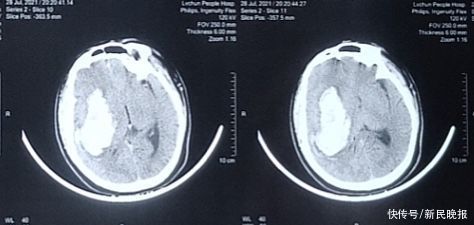

7月28日晚上8时许,云南省绿春县人民医院急诊科120送来了一位高血压脑出血的病人,患者中年男性,入院时神志不清,呼之不应,已深度昏迷,急诊外科医生评估下来患者GCS评分8分。急诊科完善CT检查,发现患者右侧大脑半球靠近基底节区大面积出血,量约100ml,中线向左侧偏移。这个CT结果愁坏了家属和急诊外科医生,这样大量的出血,绿春县人民医院没有成功救治的先例,要么放弃治疗回家,要么转诊到约4小时车程外的州府蒙自市,但转院路途遥远,患者目前情况危急,生命危在旦夕,风险太高。

当班的急诊外科医生此时想起了院里来自上海的援滇医生——复旦大学附属儿科医院神经外科对口支援的余建忠,立刻拨通了余医生的电话,余建忠医生知情后立即赶赴急诊科,评估病情后建议急诊手术。余建忠医师评估了患者影像学的情况,决定给患者进行去骨瓣减压颅内血肿清除引流术,完善术前准备后,急诊手术按计划顺利进行。余建忠医生和绿春县人民医院神经外科团队术中克服了医院手术器械设备条件的限制,经过2个多小时的辛苦奋战,顺利完成了这台绿春县人民医院第一例高血压大量脑出血的开颅手术。术后患者转ICU进一步治疗,目前患者已清醒,能自主睁眼并能遵嘱动作,恢复良好。